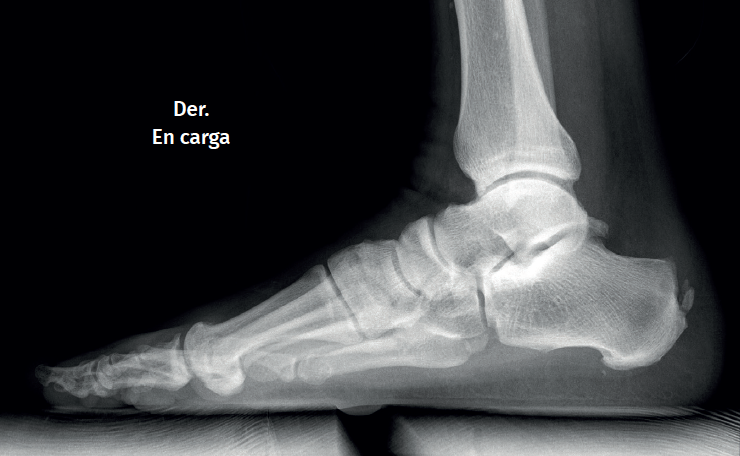

The dorsoplantar and sagittal views of both feet under loading conditions are indicated, together with the posteroanterior view of the ankles under loading conditions.

Figure 3. Plain radiography, Sagittal view with weight-bearing. Moderate calcifications in the insertion of the Achilles tendon with intratendinous enthesophyte. Morphological alterations of the posterior tuberosity of the calcaneus.

Plain radiography under loading conditions is the essential initial diagnostic tool(20). It allows us to assess alignments and dysmetria, to measure angles, to determine the morphology of the calcaneus and its posterior tuberosity, to characterise bone exostosis and increments in thickness of the retrocalcaneal soft tissues, and to plan surgical procedures (Figure 3).